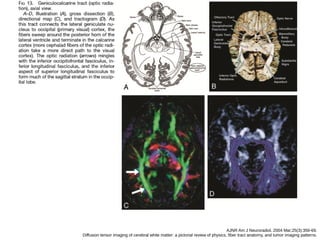

A, cíngulo

B, fascículo occipitofrontal inferior e longitudinal inferior.

AJNR Am J Neuroradiol. 2004 Mar;25(3):356-69.

Diffusion tensor imaging of cerebral white matter: a pictorial review of physics, fiber tract anatomy, and tumor imaging patterns.

●Fascículo occipitofrontal superior

● Enquanto o cíngulo reveste o aspecto superior

do corpo caloso, o fascículo occipitofrontal

segue em baixo

● Conecta o lobo occipital com o frontal,

estendendo-se posteriormente ao dorso do

núcleo caudado, paralelo ao longitudinal

superior, separado pela coroa radiada e

cápsuloa interna